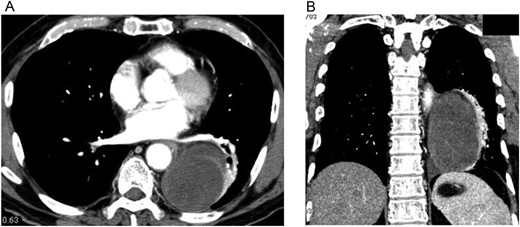

A 74-year-old man was referred to our hospital after a left middle and posterior mediastinal tumor was detected on computed tomography (CT) performed as an examination for dry cough in other hospital. CT about 2 years earlier had shown a 3.2 × 2.4-cm lipomatous tumor at the left hilum adjacent to the left lower pulmonary vein (Fig. 1), and that lipomatous tumor was considered the origin of the present mediastinal tumor. Contrast-enhanced CT performed in our hospital showed a heterogeneous tumor, displacing the left lower lobe of the lung, and measuring 10 × 7.4 × 6 cm on horizontal and coronal sections (Fig. 2A and B). Magnetic resonance imaging showed a hyperintense marginal region with central hypointensity on T1-weighted imaging, and heterogeneously high intensity in the whole tumor on T2-weighted imaging. We scheduled surgical resection, and the patient was admitted to our hospital 3 weeks after the first visit. Chest radiography showed rapid growth of the left intrathoracic tumor (Fig. 3A and B), and CT revealed a tumor measuring 11.4 × 8 × 6.2 cm without pleural effusion or hemothorax.

Contrast-enhanced CT of the chest shows an oval, smooth-shaped, heterogeneous tumor displacing the left lower lobe of the lung, measuring 10 × 7.4 × 6 cm on horizontal (A) and coronal (B) sections without pleural effusion or hemothorax.